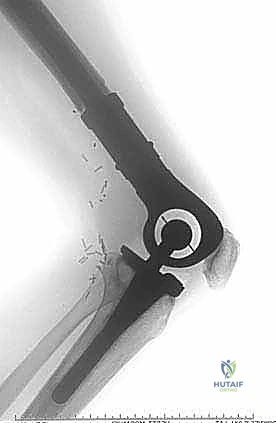

نقائل العظم الفخذي هي أورام ثانوية تنتشر إلى عظم الفخذ، مسببة الألم والكسور. يشمل علاجها الجراحي استعادة الوظيفة وتخفيف الألم من خلال التجريف والتثبيت بمسامير نخاعية أو الاستئصال وإعادة البناء بأطراف صناعية، ويتم ذلك على يد خبراء مثل الأستاذ الدكتور محمد هطيف في صنعاء.

الخلاصة الطبية السريعة: نقائل العظم الفخذي هي أورام ثانوية تنتشر إلى عظم الفخذ قادمة من أورام أولية (مثل الثدي، البروستاتا، الرئة، الكلى، أو الغدة الدرقية)، مسببة الألم المبرح والكسور المرضية التي تقعد المريض عن الحركة. يشمل العلاج الجراحي المتقدم استعادة الوظيفة، الحفاظ على استقلالية المريض، وتخفيف الألم بشكل جذري من خلال تقنيات مثل التجريف والتثبيت بمسامير نخاعية مع الأسمنت العظمي، أو الاستئصال الواسع للورم وإعادة البناء بأطراف صناعية كبرى (Megaprosthesis). يتم إجراء هذه الجراحات المعقدة بأعلى نسب النجاح على يد خبراء جراحة العظام والأورام، وعلى رأسهم الأستاذ الدكتور محمد هطيف في العاصمة اليمنية صنعاء، والذي يجمع بين الخبرة الأكاديمية والمهارة الجراحية الدقيقة.

هذا الجزء يتسع ليشكل اللقمتين الفخذيتين (Condyles) اللتين تتمفصلان مع عظم الظنبوب (القصبة) لتكوين مفصل الركبة. النقائل في هذه المنطقة تؤثر بشكل مباشر على ميكانيكا الركبة وتسبب آلاماً شديدة عند ثني أو فرد الساق. الجراحة هنا تتطلب دقة متناهية للحفاظ على أربطة الركبة (الصليبية والجانبية) أو استبدال المفصل بالكامل بمفصل صناعي للأورام إذا كان التدمير العظمي واسعاً.